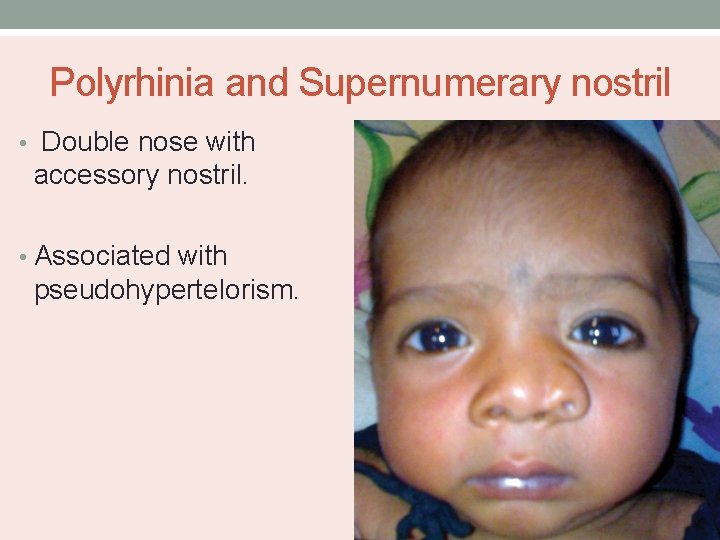

Polyrhinia and Supernumerary nostril • Double nose with accessory nostril. • Associated with pseudohypertelorism.

• Due to incomplete development of frontonasal process. • Medial nasal processes and septum are duplicated. • Anterior septal duplication with duplicated nasal passageways and postnasal defects like choanal atresia.